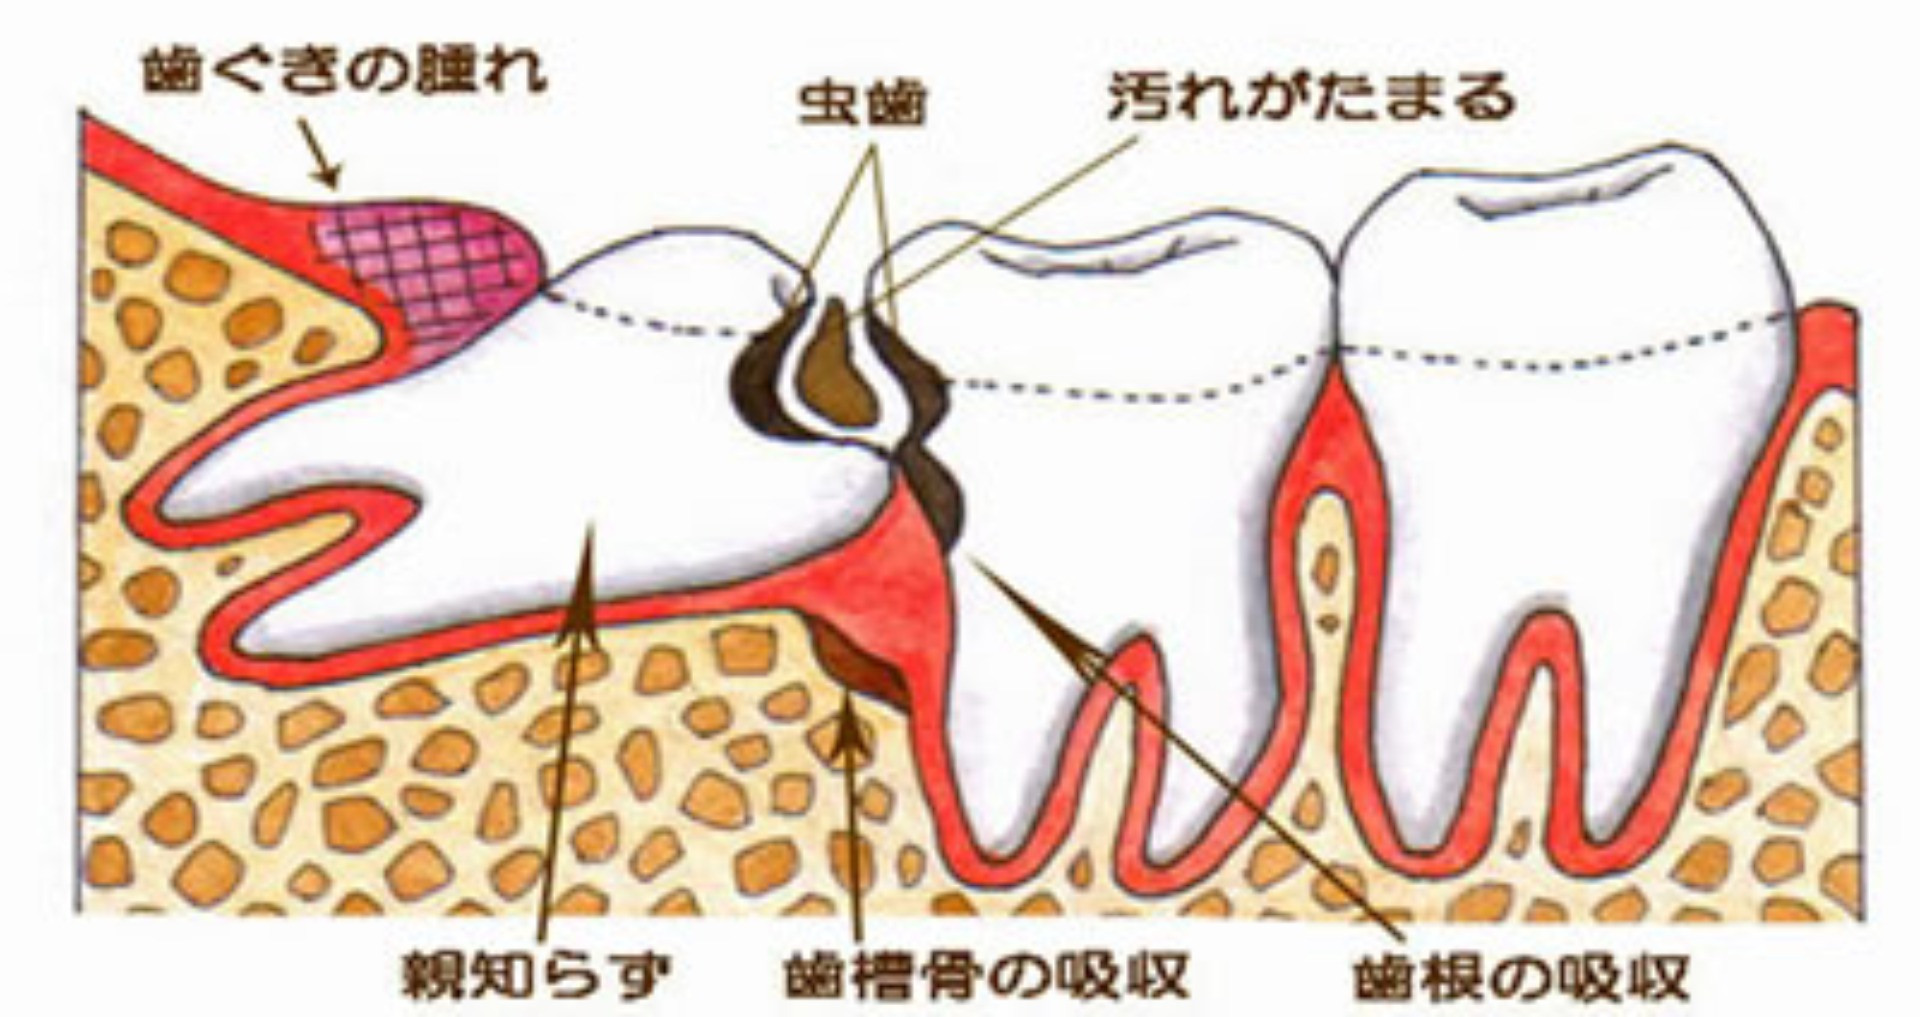

親知らずが生えてくると、虫歯でもないのに痛むことがあります。

現代の人のアゴの骨は進化して小さくなってきています。しかし、歯の大きさは昔の人とあまり変わってはいません。ですから、最後に出てくる「親知らず」は、出てきたくてもスペースが狭く、正常には出てこない場合が多いのです。 下に挙げる図のように、一部分だけ頭を出しているだけであったり、斜めに傾いて出たり、アゴのなかで水平になったままのこともあります。 |

また、下の親知らずが正常に出てこない時、上の親知らずは正常であっても、上下がしっかり噛み合っていないため、どんどん上の親知らずが下がってきて、下の歯肉に当たるようになります。 本来、歯はなるべく抜かずに残したいものです。しかし親知らずに関しては、残しておいて悪いことはしても、いいことは何もないのです。